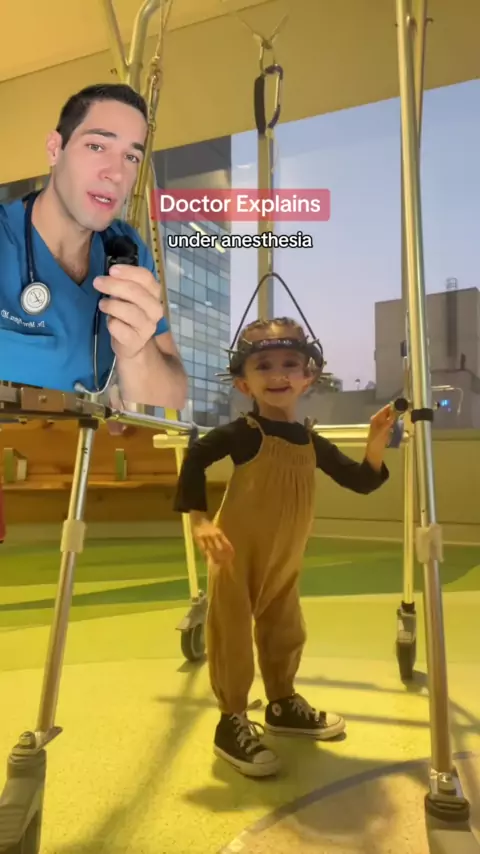

A tração endireita a coluna para facilitar a cirurgia e, assim, diminuir o risco # duet with

8